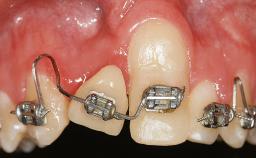

Implant Placement in the Esthetic Zone and Coverage of Multiple Gingival Recessions

This case illustrates use of a modified ‘tunnel’ technique, which has been shown to be highly effective in root coverage procedures. The tunnel technique is used to achieve soft-tissue augmentation across the anterior area, including the planned implant site, using collagen matrix as grafting material. The patient is a 47-year-old woman with high esthetic expectations. Her main concern was the appearance of the anterior teeth and their “elongation”.

Soft Tissue Grafting Staged